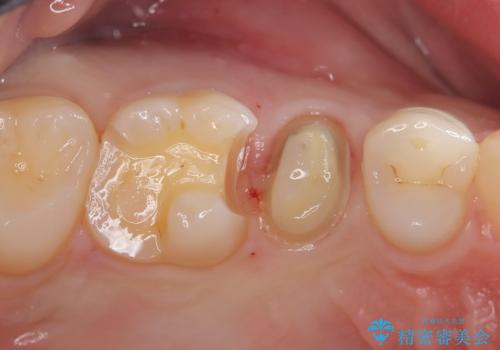

- 定期検診にて虫歯を発見したため、セラミッククラウン、セラミックインレーにて治療を行いました。

小臼歯の虫歯は歯髄に近かったため、部分的断髄法にて歯髄を部分的に保存した治療をおこなっています。

部分的断髄法を行う際は

・自発痛の既往

・冷温刺激に対する長引く疼痛

・打診

にて診断をおこない、治療が可能かどうかを判断します。